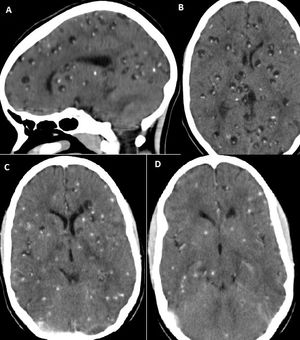

신경낭미충증의 뇌 CT 치료 전(A 및 B) 및 후(C 및 D) 알벤다졸 치료

신경낭미충증은 감염 후 증상이 수개월 또는 수년 후에 나타나는 경우가 많다. 따라서 기생충 제거는 응급 상황이 아니며, 초기 치료는 증상 완화를 목표로 한다. 항간질제, 항부종제, 진통제, 소염제 등을 사용하며, 카르바마제핀은 발작 조절에 흔히 사용된다. 항간질제는 발작이 없는 상태로 1년까지 사용할 수 있다. 두개내 고혈압은 수술, 아세타졸아미드, 스테로이드, 만니톨 등으로 관리할 수 있다.

가장 흔히 사용되는 구충제는 알벤다졸(기생충의 포도당 흡수 및 대사 억제)과 프라지콴텔(기생충의 칼슘 경로 및 항상성 변화를 통해 마비 유발)이다. 구충제는 며칠에서 몇 달에 걸쳐 작용하며, 생존 낭포나 초기 교질 낭포 단계의 낭포에만 효과가 있다. 석회화된 낭포에는 효과가 없으며, 거미막하 신경낭미충증이나 뇌염 신경낭미충증과 같이 수두증 발생 위험이 있는 경우에는 투여할 수 없다. 이러한 경우 치료 후 발생하는 염증은 두개내압을 급격히 상승시켜 사망에 이르게 할 수 있다.

알벤다졸은 단일 뇌 실질 내 낭포 환자의 간질 발작 재발을 감소시키는 것으로 나타났다.[9] 간질 발작 외 증상이 있는 환자의 발작 예방에 대한 항간질약의 효과 및 치료 기간은 추가적인 무작위 대조 시험이 필요하다.[10]